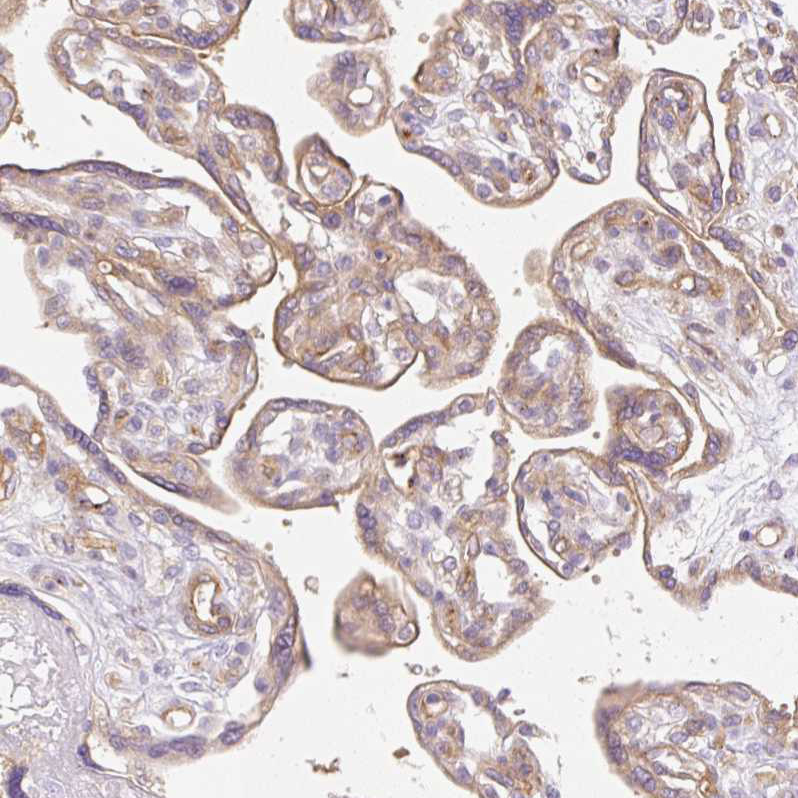

Immunohistochemical staining of human kidney shows strong membranous positivity in cells in glomeruli.